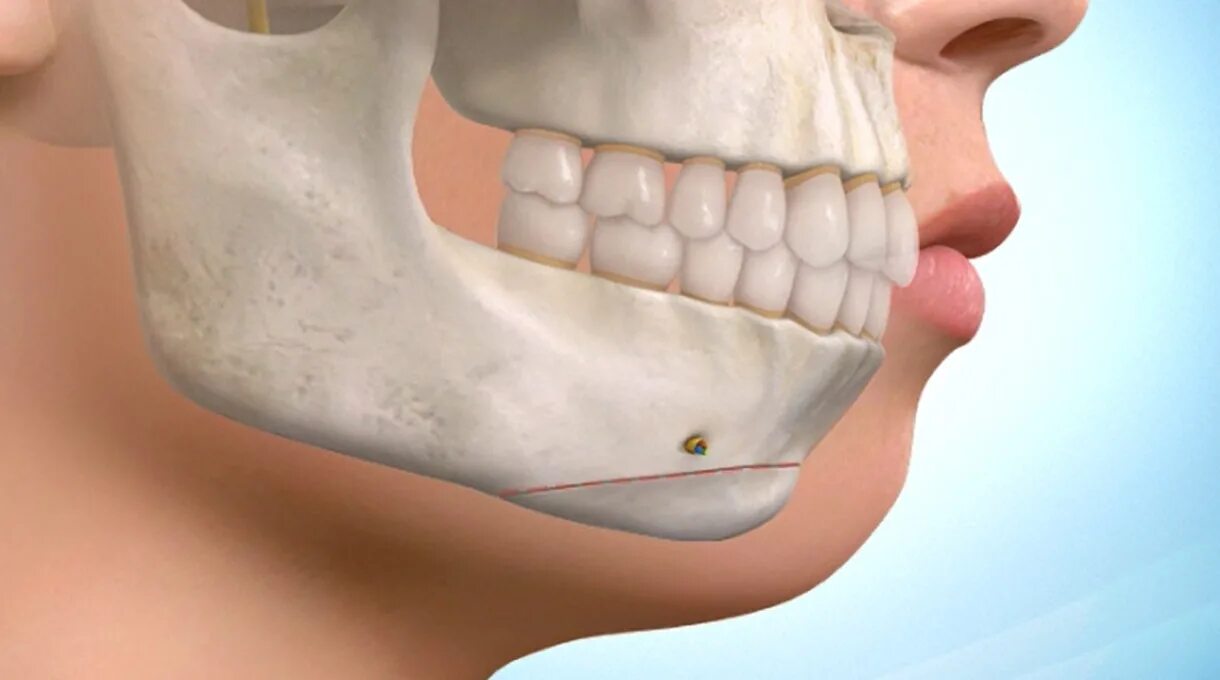

Трясет челюстью